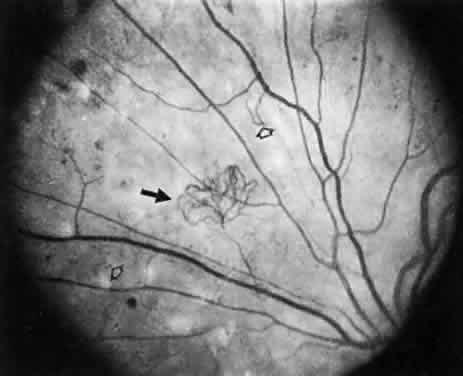

After years of background diabetic retinopathy, patients progress to develop a more visually threatening disorder known as proliferative diabetic retinopathy (Fig. 3). The Diabetic Retinopathy Study, performed between 1972 and 1975, found that blindness from proliferative diabetic retinopathy can be significantly reduced by satisfactory photocoagulation treatment. In the Diabetic Retinopathy Study, 1758 patients were studied with randomization of laser treatment to one eye and the fellow eye assigned as a control. In 28 months, blindness developed in 16% of the untreated control eyes that had neovascularization at the start of the study. Such a result was found in only 6.4% of treated eyes.44 This therapeutic result was so positive that this has become the standard of therapy in the United States. In general, this treatment consists of 1200 moderate-intensity photocoagulation spots applied to the midperiphery. This therapy is performed at a laser spot size of 500-μm diameter for each application, and each spot is applied at 500 μm from its nearest neighbor. This allows enough clear, untreated retina between each application to permit areas of residual function that reduce the risk of a compromised peripheral visual field. Often, this treatment is not applied in one sitting because of patient and physician discomfort. Instead, it is initiated and becomes a part of a series of two or three treatment sessions, each about 1 week apart (Fig. 4). In addition to preventing blindness, the Diabetic Retinopathy Study was able to identify the features of diabetic retinopathy that are associated with an increased risk of blindness. These risk factors were described as follows:

Fig. 3. Neovascularization (closed arrow) and intraretinal microvascular abnormalities) (open arrowheads).

Fig. 4. Pan-retinal photocoagulation with 1200 to 1600 500-μm spots.